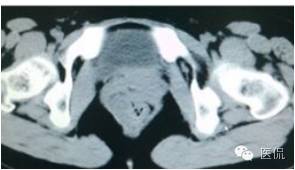

增强延迟期(CT值106HU)